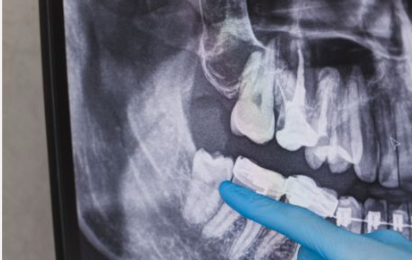

Before a dentist removes anything, they need to see what is happening under the surface. A panoramic X-ray shows the exact position of each wisdom tooth, how deep it sits, which direction it is growing, and whether it is pressing against the roots of your other teeth.

This step matters more than most people realize. Two patients can have the same complaint and end up needing completely different procedures. One may walk out in 20 minutes. The other may need a full surgical extraction with stitches. The X-ray determines which path your treatment takes.